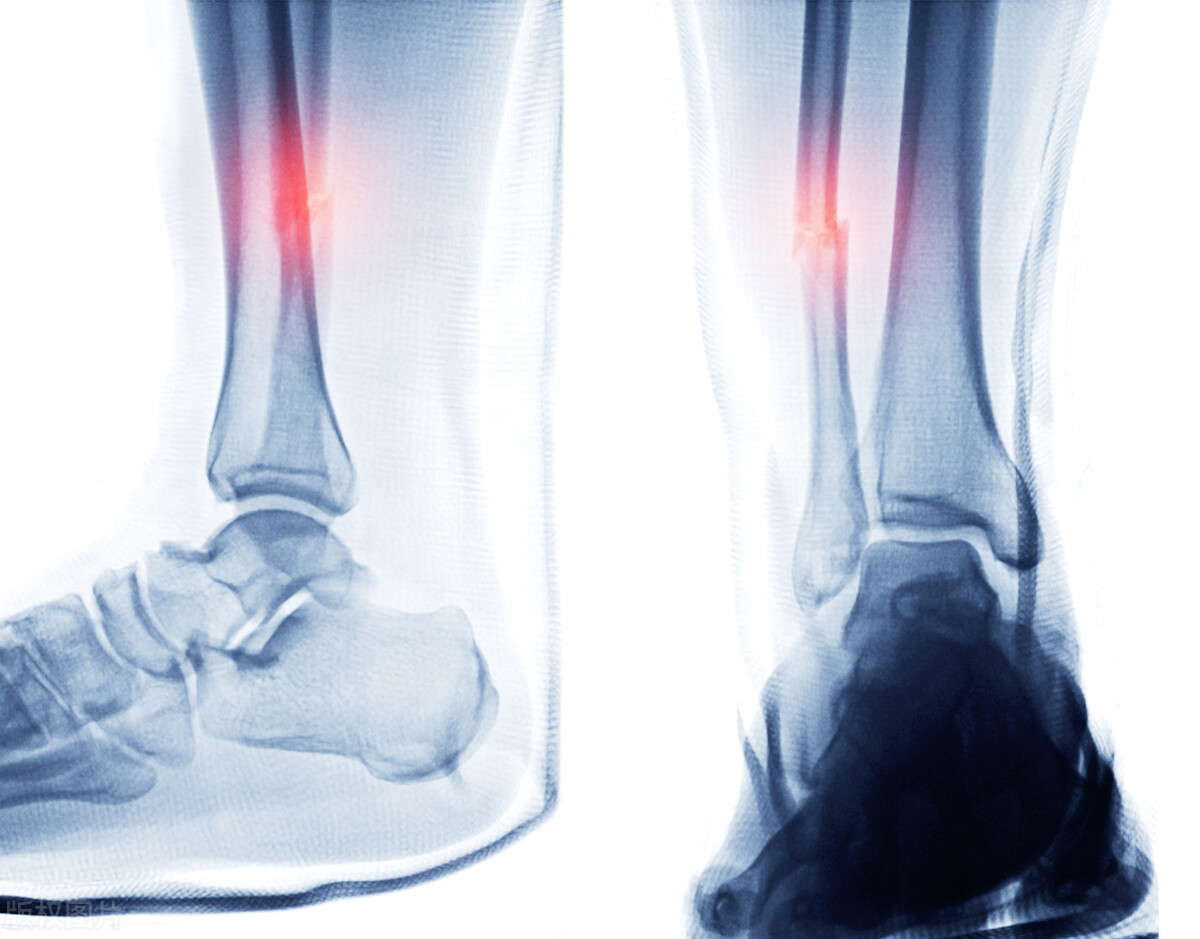

脚踝骨折,开始没事后来却很疼,怎么回事

来自襄阳的一 位 5 3 岁男性患者,右脚踝外侧骨折,在医院固定 后 1 0 天后,慢慢开始疼痛难受,并且越来越严重,晚上有时疼的睡不着,想问问怎么回事。我看了他的情况,不严重,也服用了医院开了消炎止疼的药物,但为什么会出现开始不疼,后来越来越疼的情况呢?